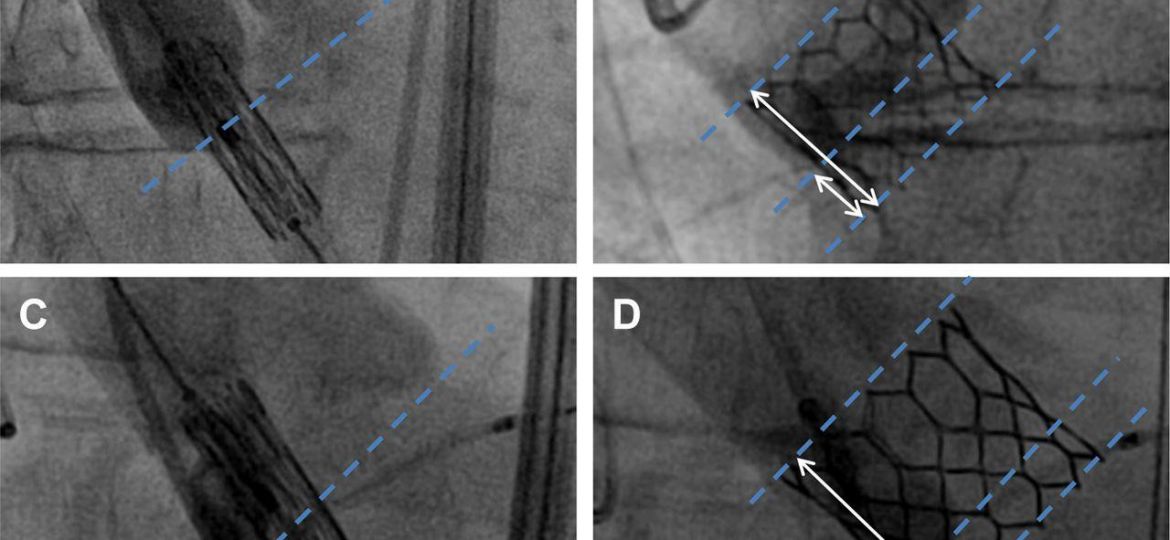

Desde o primeiro relato em 2002, o implante transcateter de valva aórtica (TAVI) tem sido selecionada e, em alguns casos,…